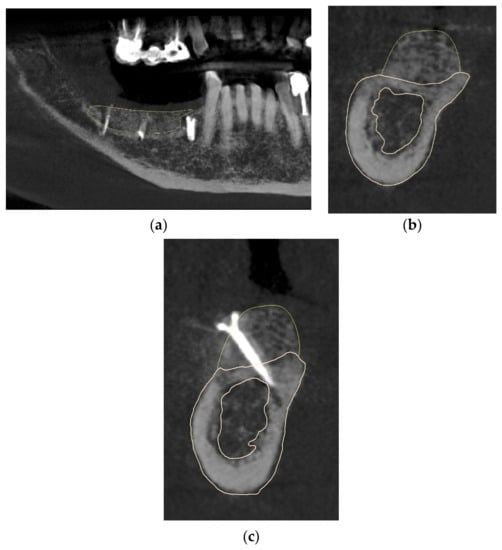

The postoperative evaluation confirmed no resorption after 5 months compared to the preoperative design of the bone block (Figure 11a). The yellow lines on the CBCT images show the design of the bone block, demonstrating no loss of volume after 5 months (Figure 11b,c).

Figure 11.

(a–c) CBCT analyses showing the results vs. design (yellow lines).

We were able to show an increase of the bone in the horizontal dimension of 7.38 mm and at a vertical height of 6.86 mm (Figure 12a,b).

Figure 12.

(a,b) The results in bone gain in width and height.